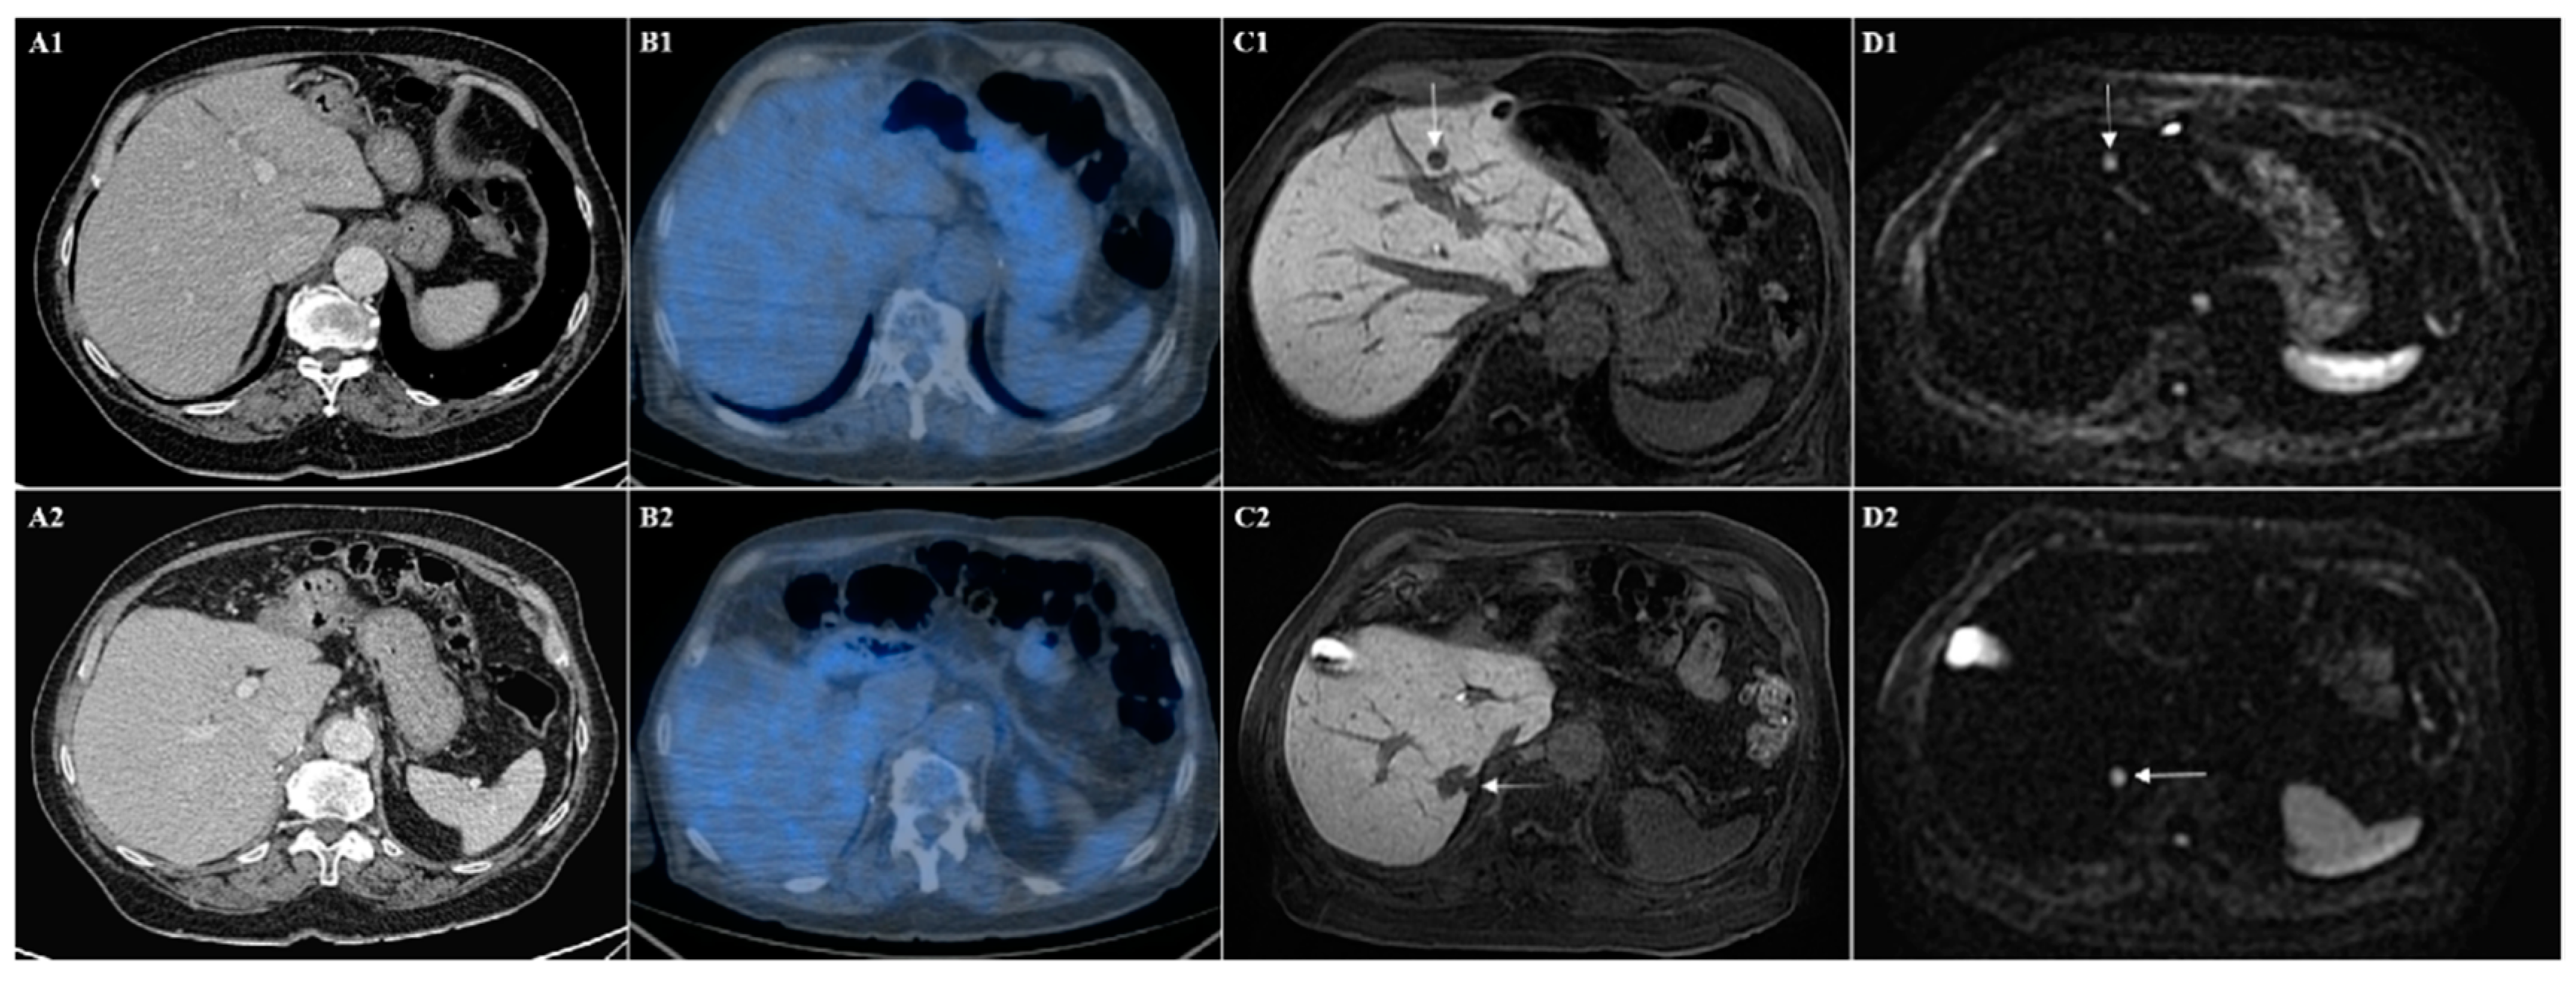

Figure 2.

(A) CT and (B) PET-CT images show the absence of liver metastases in different liver section (1 and 2). (C) Hepatobiliary phase of Gd-EOB-DTPA MRI and (D) diffusion-weighted imaging show in the same patient the presence of two liver metastases from sarcoma in two different levels, one in the segment III (arrows in (C1) and (D1)) and one in the segment VII (arrows in (C2) and (D2)).